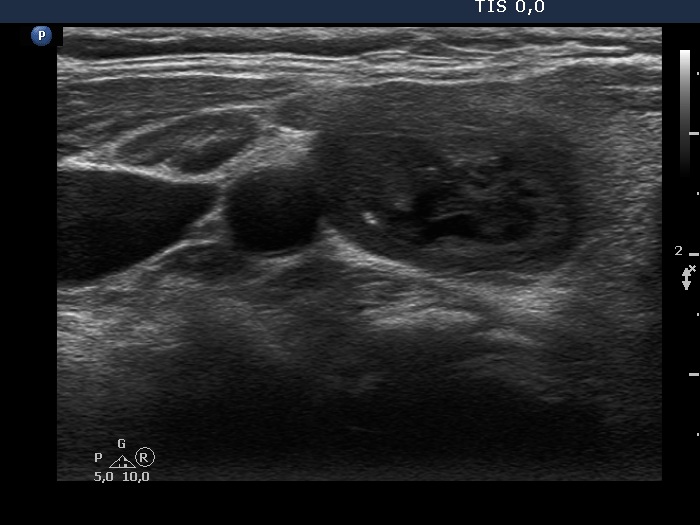

Ultrasonography. The thyroid was echonormal. There was a mixed moderately hypoechogenic-cystic nodule in the right lobe. The lesion presented various intranodular hyperechogenic granules including back wall figures, non-specific granules and a few typical comet-tail artifacts. There were other, difficult-to-classify bright granules. The latter could be either comet-tail artifacts or microcalcifications. There were several moderately hypoechogenic lesions in the left lobe.

3 mL brown fluid was aspirated. Cytology resulted in benign cystic degeneration.